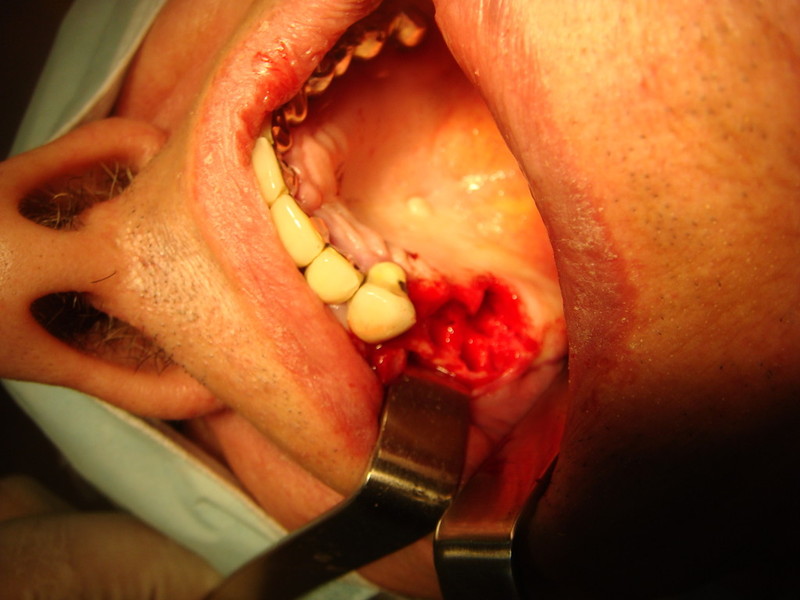

Estrazione di un canino incluso e contestuale inserimenti di impianto e innesto osso eterologo